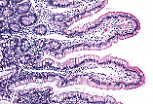

Les

tuniques fondamentales du tube digestif se retrouvent au niveau de cet iléon humain à

savoir la muqueuse, la sous-muqueuse, la musculeuse et la séreuse.

Les replis de la muqueuse ( valvules conniventes) et les villosités sont des dispositifs d'amplification de la surface d'absorption. |

La muqueuse de l'iléon est caractérisée par des villosités qui font protrusion dans la lumière. Des glandes tubulaires, glandes de Lieberkühn, s'étendent de la base des villosités jusqu'à la musculaire muqueuse. Le chorion est riche en éléments lymphoïdes. |

La forme

des villosités iléales varie d'une espèce animale à l'autre, en fonction du régime

alimentaire.

Chez l'homme et les carnivores, elles sont digitiformes. Cette image est tirée d'un iléon de jeune rat en régime lacté. |